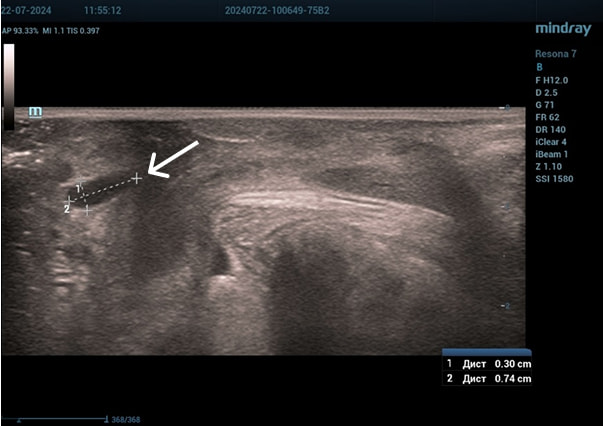

Осмотр: периуретрально визуализируется мягко-эластичное образование размерами 0,5×0,5 см.

Диагноз: хронический цистит (посткоитальный). Дистопия уретры. Опущение передней стенки влагалища I степени. Состояние после периуретрального введения геля на основе гиалуроновой кислоты.